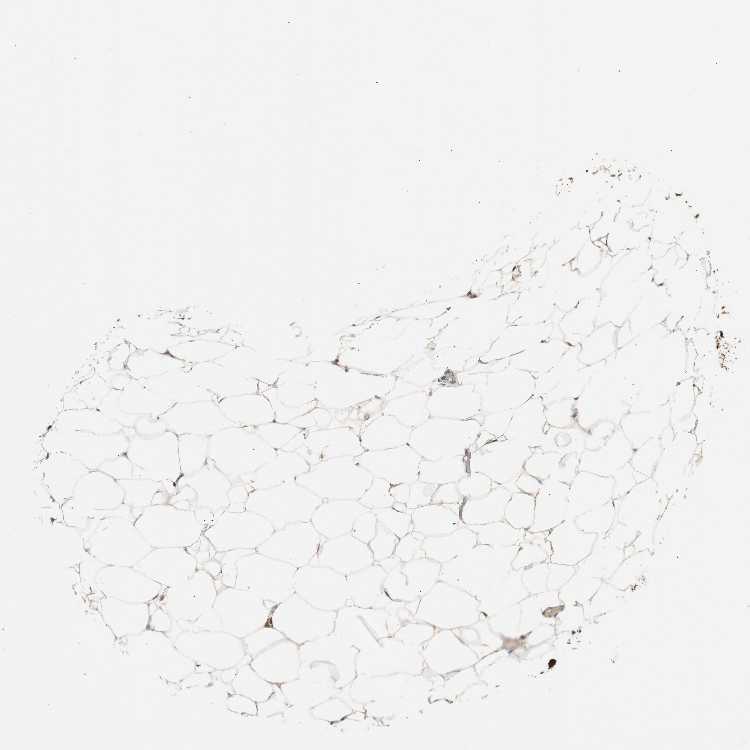

SOFT TISSUE 1 - Antibody stainingi

Antibody staining in the annotated cell types in the current human tissue is reported as not detected, low, medium, or high, based on conventional immunohistochemistry profiling in selected tissues. This score is based on the combination of the staining intensity and fraction of stained cells.

Each image is clickable and will lead to virtual microscopy that enables deeper exploration of all samples and also displays staining intensity scores, fraction scores and subcellular localization as well as patient and tissue information for each sample.

Antibody HPA003156

Chondrocytes Medium

Fibroblasts Not detected

Peripheral nerve Low

SOFT TISSUE 2 - Antibody stainingi

Fibroblasts Medium